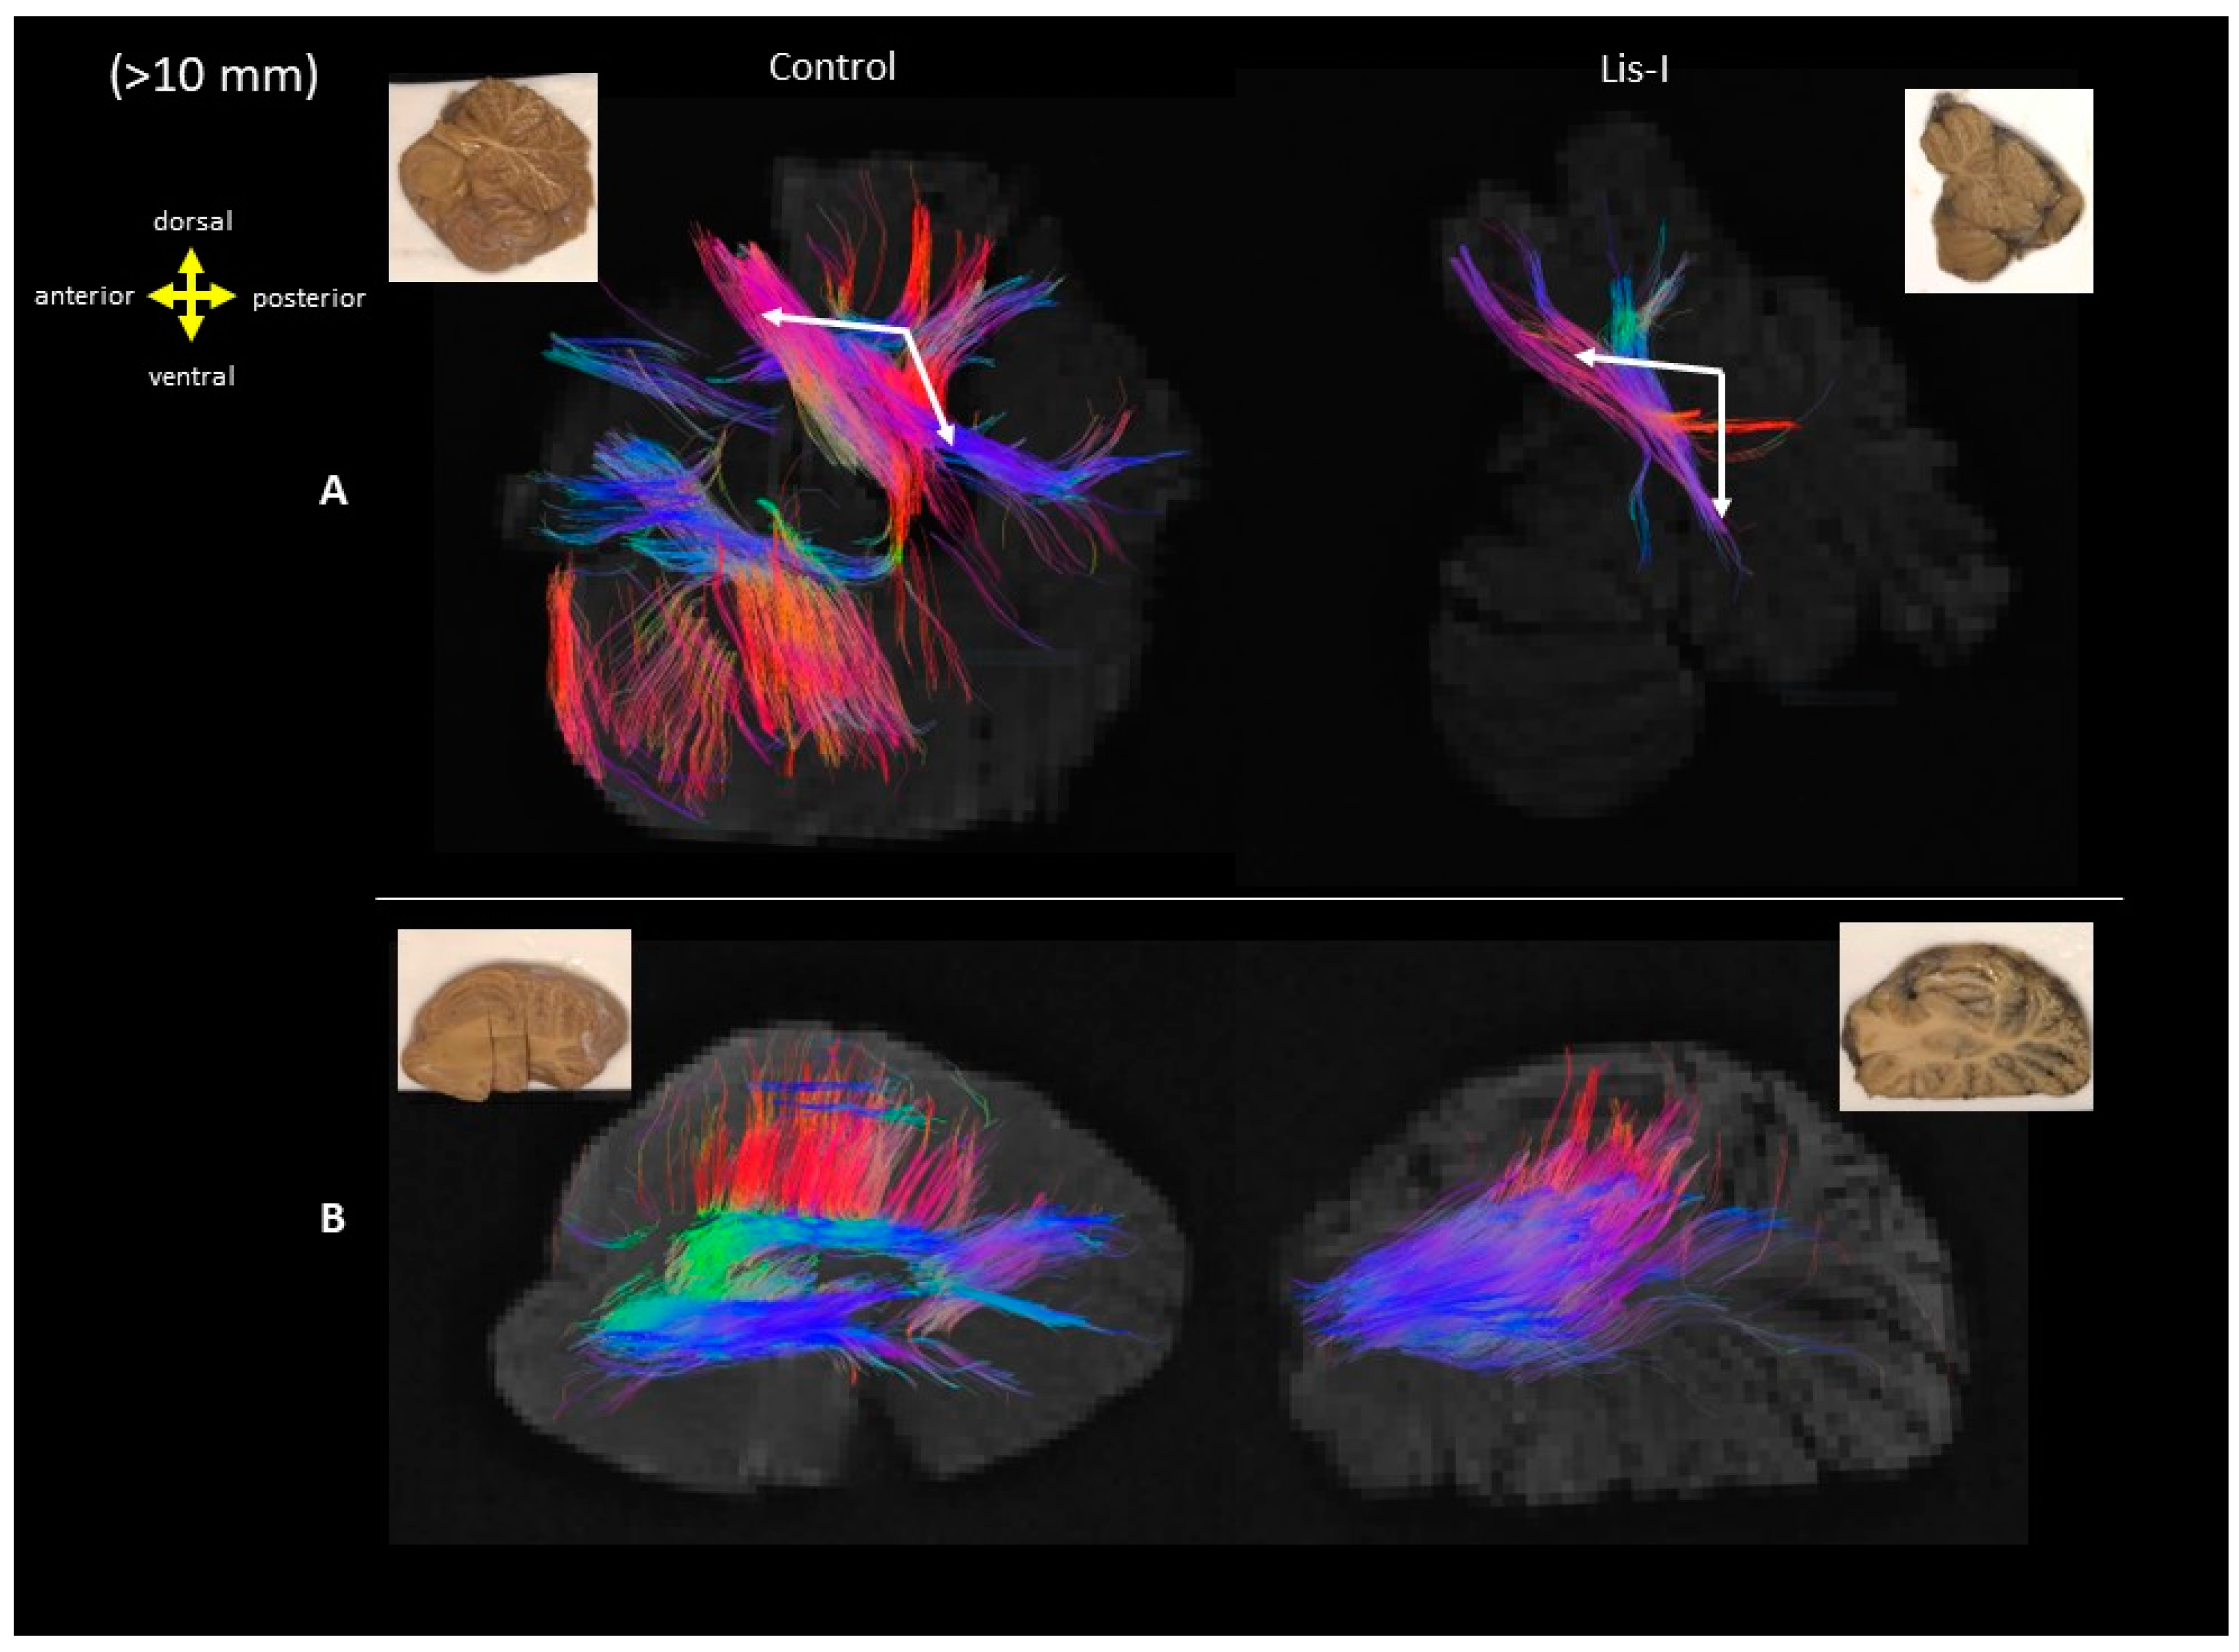

3. Results

4. Discussion

4.2. Microanatomy of Lissencephaly